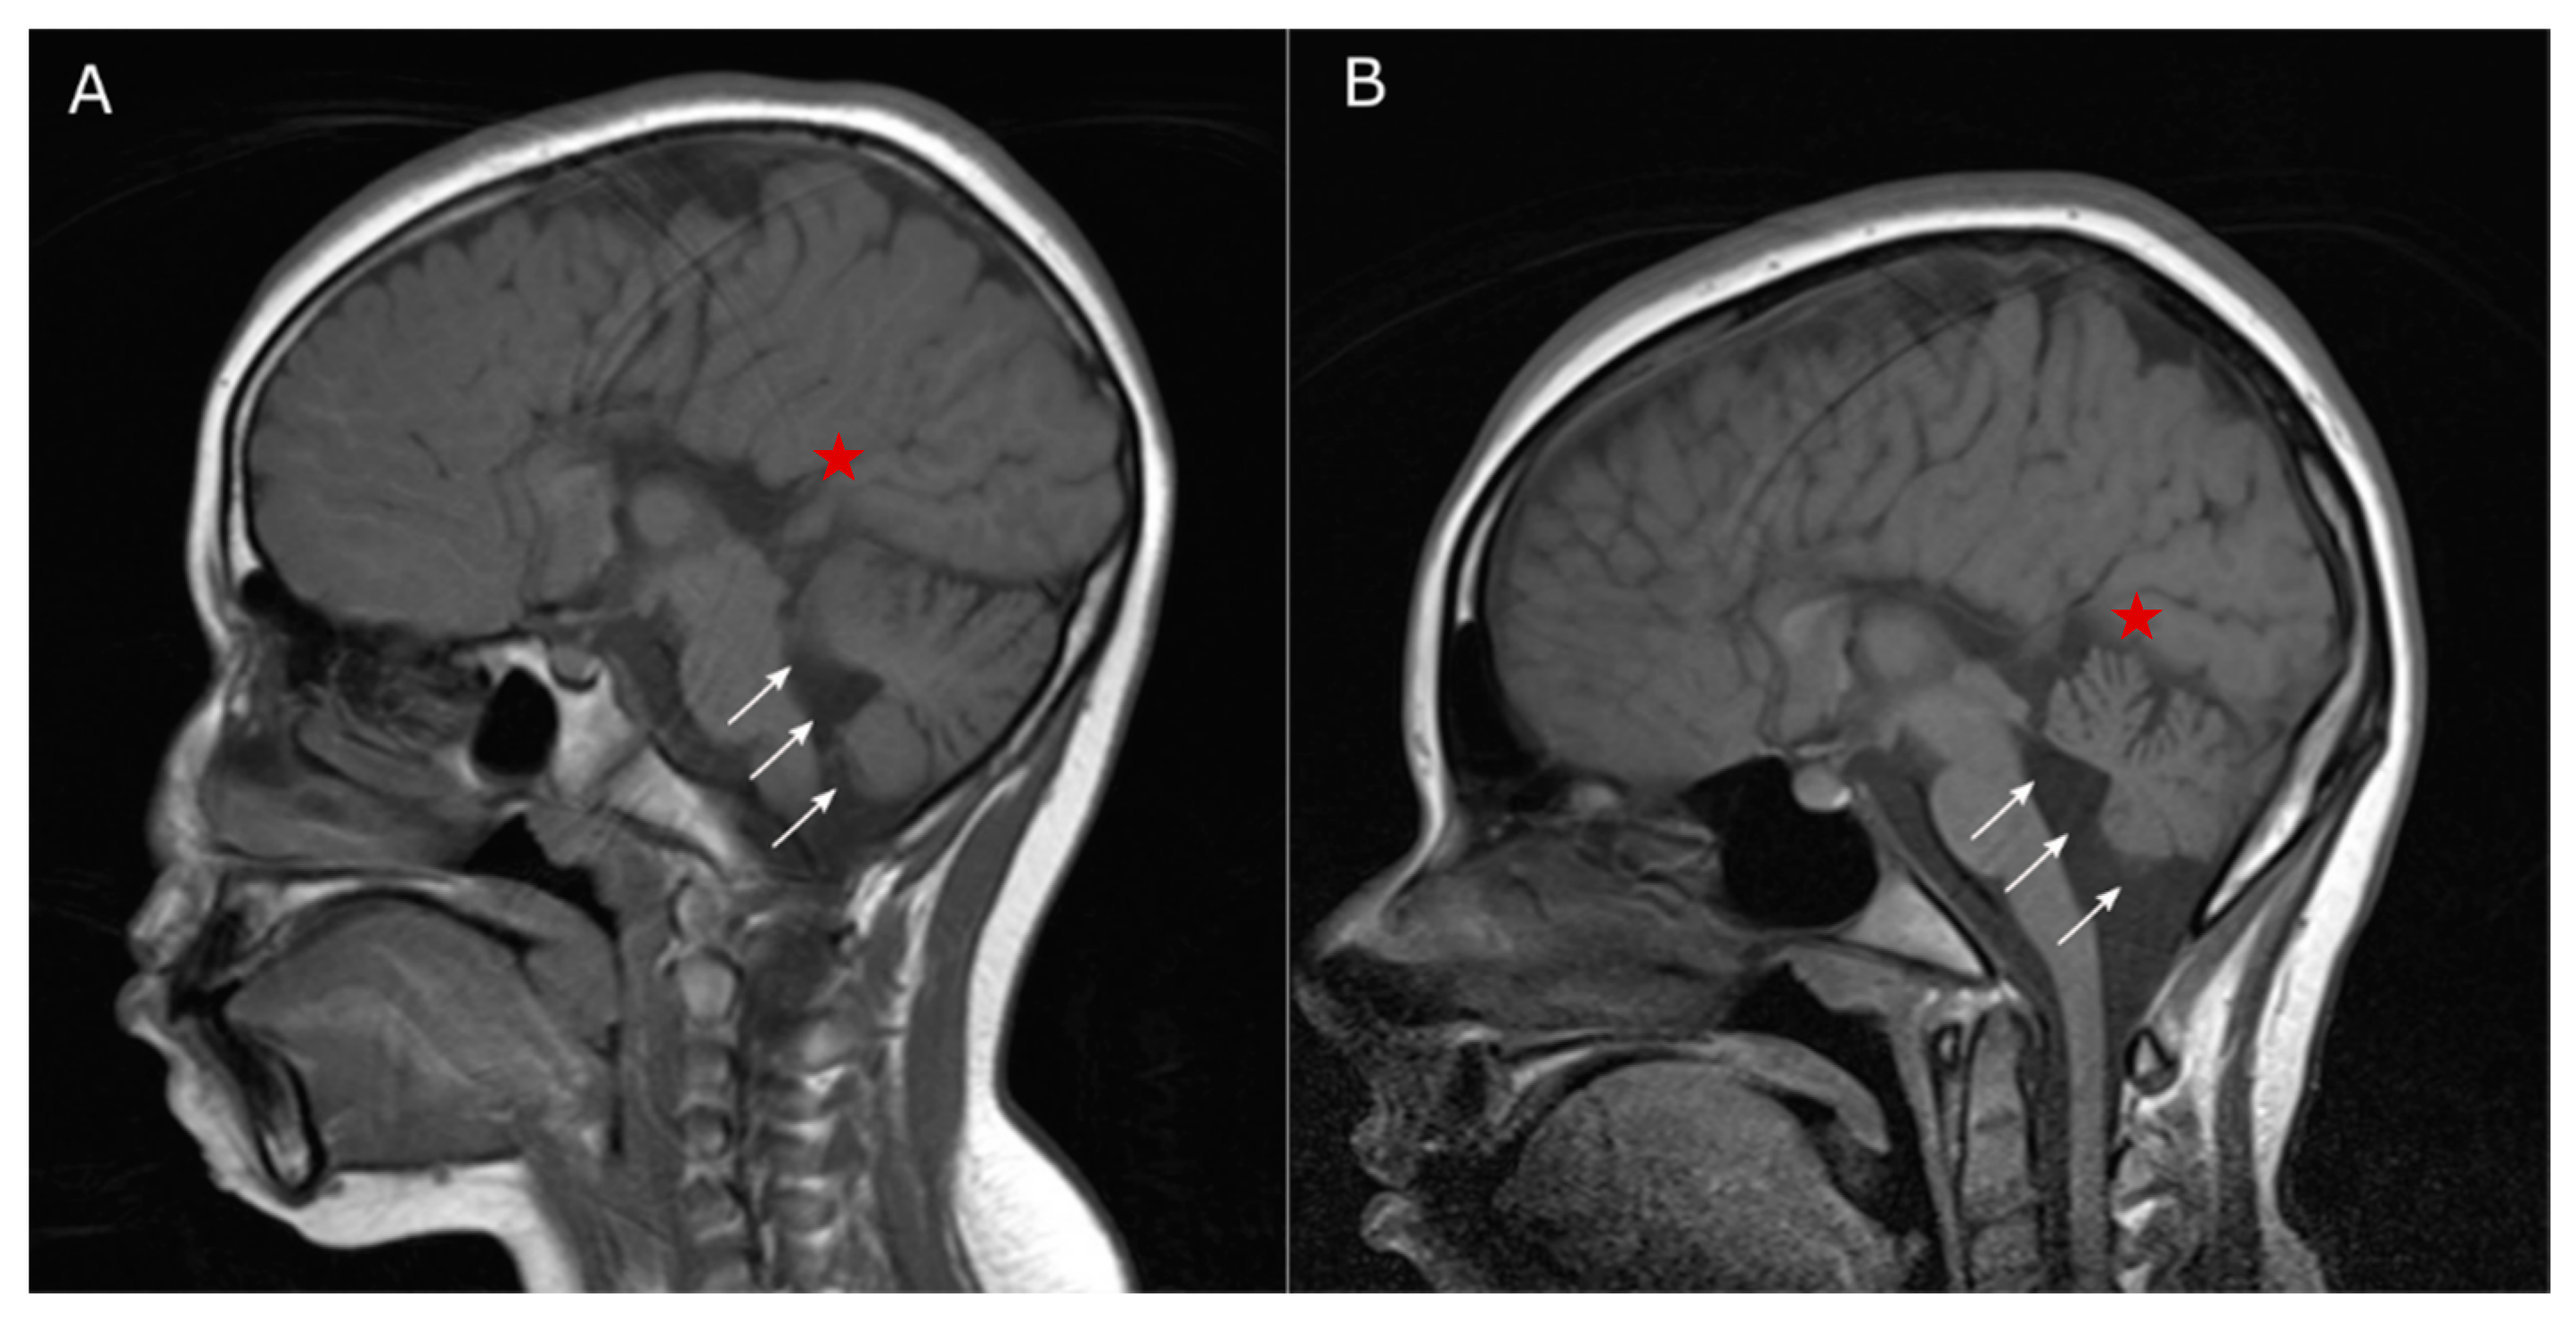

2.2. Clinical Profile